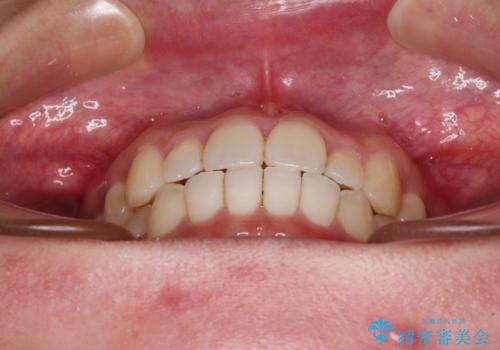

すきっ歯とオープンバイトをインビザラインで改善

- 前歯の上下スペースと前歯の隙間を気にして来院された患者様です。

インビザラインにより上下の前歯の隙間を閉じていくこととしました。

上下の隙間に舌が入り込むことが、すきっ歯やオープンバイトの原因であったため、舌の筋肉のトレーニングも並行して行い、後戻りの抑制を図りました。